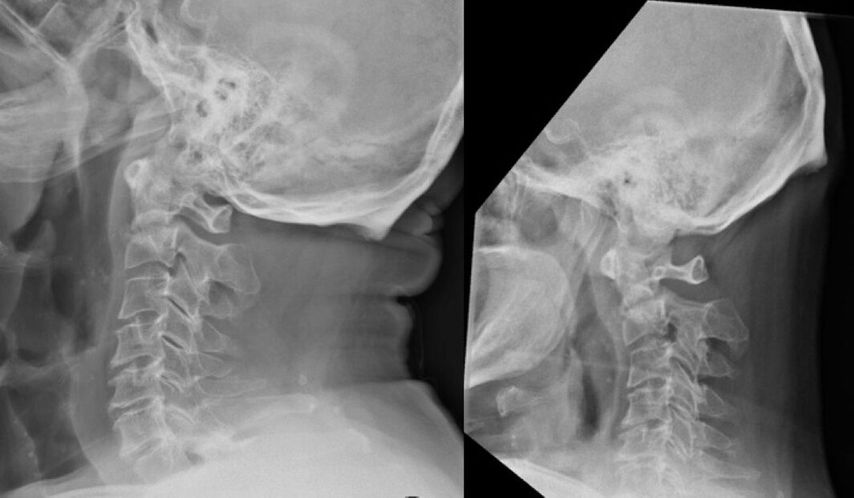

Zur Diagnostik einer Densfraktur gehört unbedingt die klinische Untersuchung. Patienten präsentieren sich meist mit Nackenbeschwerden und Einschränkung der Kopfbeweglichkeit. Vor allem ältere Patienten berichten von Stürzen aus dem Stand und weisen zusätzlich oft Prellmarken an Kopf oder Gesicht auf. Neurologische Ausfälle sind selten. Zur Standarddiagnostik zählt außerdem das Röntgen in a.p., seitlicher und transoraler Densaufnahme.19 Bei Patienten über 65 Jahre, Patienten mit Parästhesien oder nach gefährlichen Traumata, wie z.B. nach Sturz aus über 1m Höhe, axialer Stauchung des Kopfes oder Autounfall mit hoher Geschwindigkeit, wird die Durchführung einer Computertomografie empfohlen.20